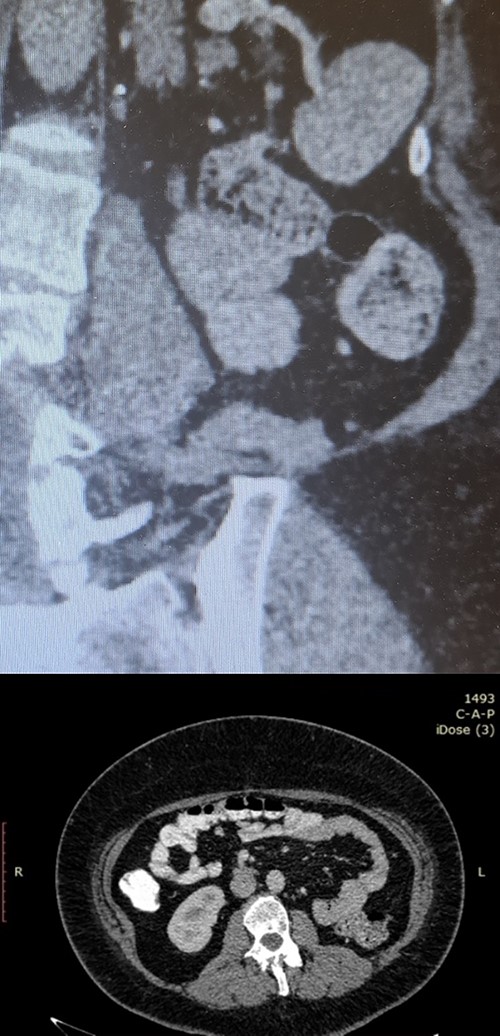

Postoperative follow-up imaging with abdomen CT at 12 months; coronal (upper side) and axial (lower side) planes, and no evidence of local recurrence, and no other pathologic finding.

A 20-year-old Caucasian woman presented herself to the outpatient department because of a mass on the left kidney. The mass was an incidental finding in an abdomen computed tomography (CT), which was suggested within the diagnostic evaluation for a persistent flank pain. In the past, she never had any pathologic urologic situation. According to the CT finding, the mass was located on the lower pole of the left kidney (83 × 111 × 111mm) and there was no other pathologic finding. Anamnestically, she had heterozygous beta Mediterranean anaemia. The patient was obese (body mass index = 33.4 kg/m2). We proceeded with a thorax CT which revealed no pathology. The patient underwent a laparoscopic nephrectomy by an urologist well trained and experienced in laparoscopy. Macroscopically, a mass in the lower pole of the left kidney (110 × 100 × 100 mm) was documented. Cut sections revealed multiple thin walled, non-communicating cysts of varying sizes with smooth lining without solid component. Microscopically, the tumor was characterized of cysts separated by thin septa. The cysts lined by single layer of flat, cuboidal and hobnail epithelium and the septa were fibrous, hypocellular to hypercellular. No mitoses or necrosis were identified. The immunohistochemical examination showed that the epithelial cells were positive for the cytokeratins AE1/AE3 and PAX-8. The stromal cells were positive for the progesterone receptors, estrogen receptors and CD10. The latter was concentrated around epithelial elements (Figs 1 and 2). These findings established the diagnosis of ACN. At the 12-month follow-up control with abdomen CT, there was no pathologic finding (Fig. 3). The patient is under urologic and nephrologic montitoring without any abnormal finding at 21 months after surgery. This research complies with the guidelines for human studies and was conducted ethically in accordance with the World Medical Association Declaration of Helsinki.